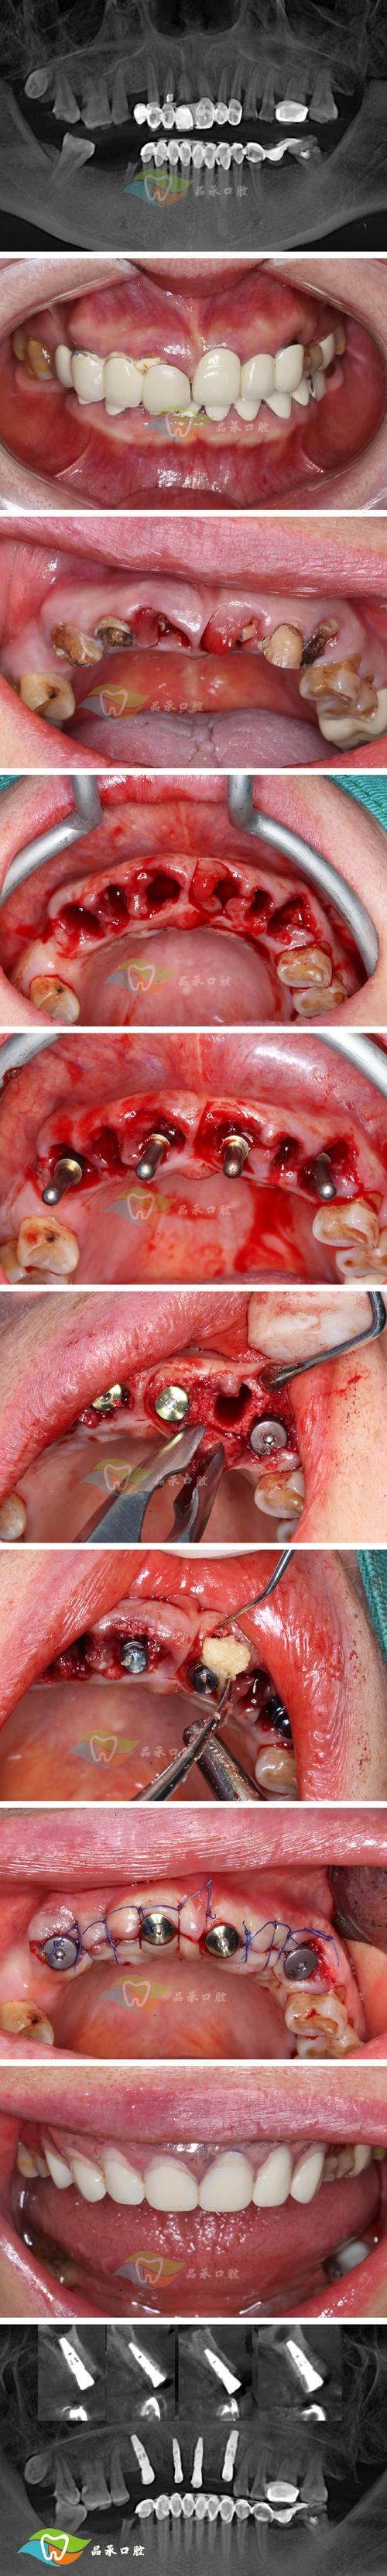

(图片来源网络,侵删)- 使用不含氟化物的抛光膏(如浮石粉糊剂)和橡皮杯/杯状刷,在低速手机下仔细清洁烤瓷牙表面,去除所有可见的污垢、菌斑、临时粘结剂残留、抛光剂残留等。

(图片来源网络,侵删)- 去除多余的粘结剂,特别是牙龈边缘和邻间隙处,避免刺激牙龈和食物嵌塞。